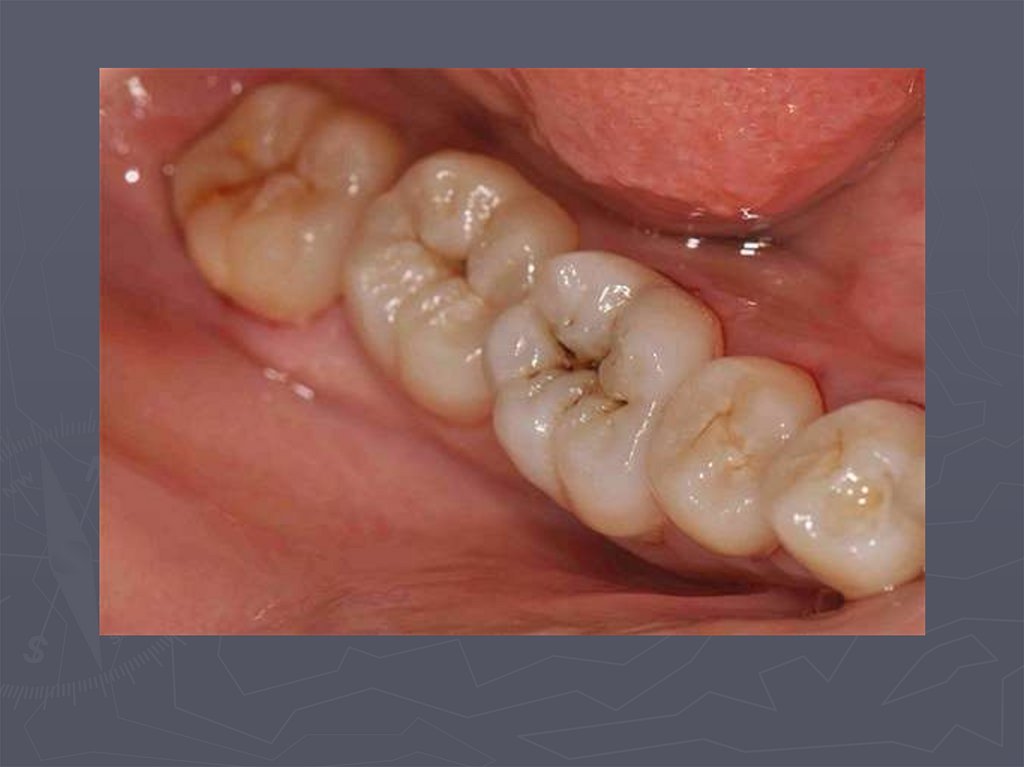

5. ОСОБЕННОСТИ КЛИНИЧЕСКОГО ПРОЯВЛЕНИЯ КАРИЕСА ВРЕМЕННЫХ ЗУБОВ У ДЕТЕЙ РАЗЛИЧНОГО ВОЗРАСТА

При клиническом осмотре выявляются:

► кариозные полости по глубине мелкие;

► имеют плоскую форму;

► входное отверстие в кариозную полость широкое

► эмаль по краям кариозной полости хрупкая;

► инфицированный дентин в полости влажный.